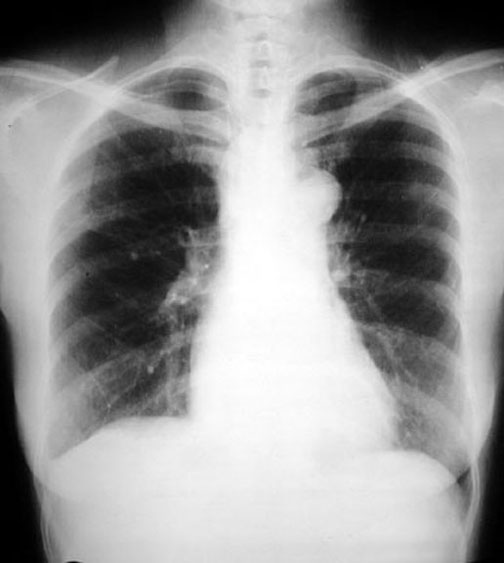

Achalasia Cardia

• Inhomogeneous cardiac density: Not demonstrable in this presentation

• Density crossing mid-line. Not demonstrable in this presentation

• Right sided inlet to outlet shadow. Not demonstrable in this presentation

• Barium swallow below: Dilated esophagus